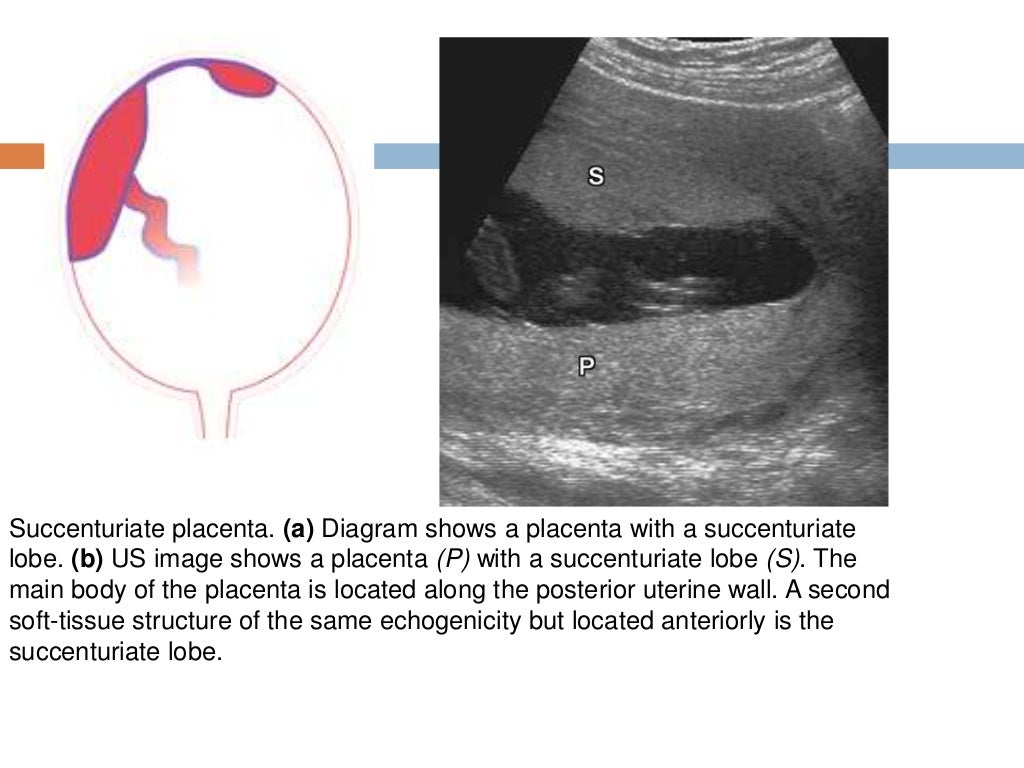

Imaging of the placenta What Is Accessory Placenta Oct 5, 2019 at 11:30 am. An accessory lobe of placenta is an addition separate lobe of placenta. Placenta accreta is the abnormal adherence of the placenta to the myometrium, associated with partial or. A succenturiate (accessory) lobe is a second or third placental lobe that is much smaller than the largest lobe. One or multiple accessory lobes connected to. What Is Accessory Placenta.